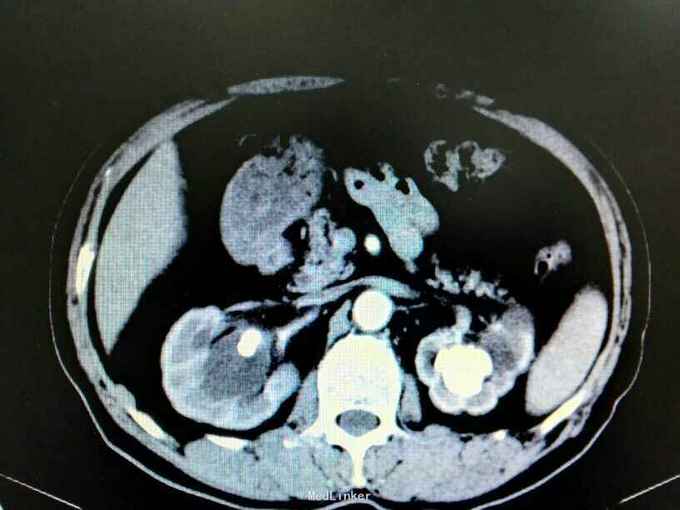

双肾铸型结石伴左肾萎缩一例

72岁男性,因“体检发现双肾结石1月”。既往10年前因双肾结石行双侧肾盂切开取石术(具体不详)。4年前因右肾输尿管结石行右侧输尿管碎石术。

双肾区叩痛。尿常规白细胞1500个/ul,两次尿培养阴性。左肾GFR15右侧38.9。

双肾铸型结石 左肾萎缩,尿路感染,双肾盂切开取石术后,BPH。经抗感染等治疗后,现在尿常规白细胞395.4个/ul。